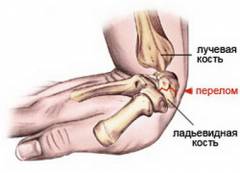

- Перелом лучевой кости в типичном месте. Около 70% переломов происходит в области дистальной головки, на расстоянии двух-трех сантиметров от суставной поверхности. Чаще всего такой перелом возникает после падения на согнутую кисть вытянутой руки и бывает косым или поперечным. Он возникает под воздействием двух векторов силы: один связан с ускорением падения, другой — с плечом, образованным кистью. Из-за остеопороза, особенно у пожилых людей, такие переломы встречаются чаще, но могут возникать и у более молодых пациентов.

- Перелом лучевой кости с вывихом головки локтевой кости. Травма предплечья часто затрагивает не только лучевую кость, поэтому переломы нередко сопровождаются повреждениями локтевой кости. Перелом нижней трети диафиза лучевой кости часто сочетается с вывихом головки локтевой кости в области дистального лучелоктевого сустава. Эта травма, известная как перелом-вывих Галеацци, требует адекватного медицинского вмешательства из-за значительных нарушений функции верхней конечности.